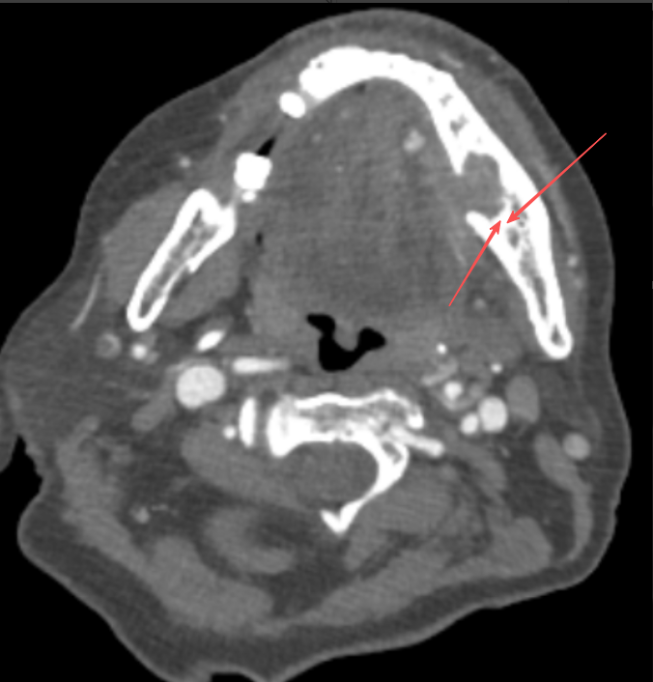

术前增强CT示肿瘤浸润破坏达骨松质

进一步检查发现,肿瘤已经突破了黏膜的边界,悄然侵入了下颌骨。“那……那怎么办?”老张的声音有些发抖。“别担心,我们还有办法。”医生的语气沉稳而坚定。